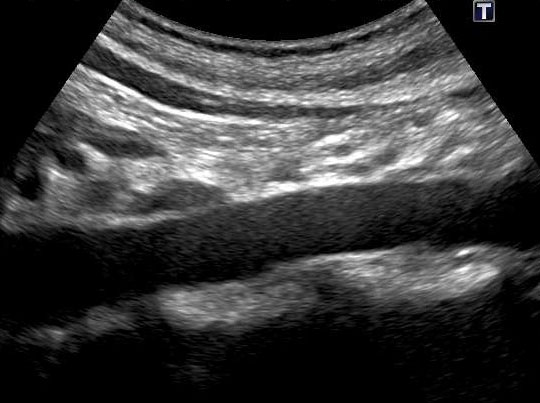

腹部⼤動脈エコー検査で、腹部⼤動脈瘤の有無と⼤きさがわかります。

正常な腹部⼤動脈のエコー画像

正常な腹部⼤動脈は太さがほぼ⼀定

腹部⼤動脈瘤のエコー画像

部分的に拡張している部位が腹部⼤動脈瘤